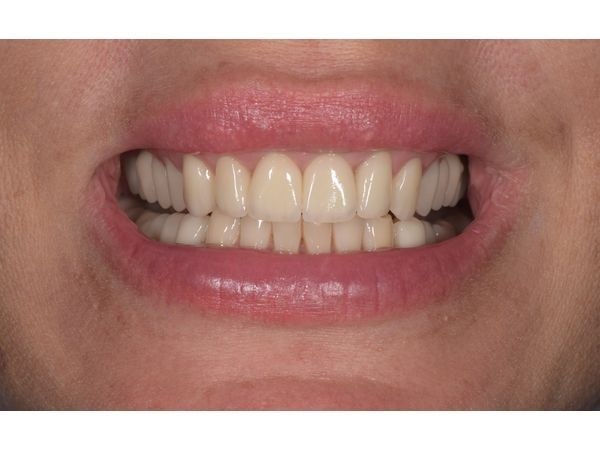

Через полгода после пластики кости и имплантации женщине установили временные фрезерованные коронки из полиметилметакрилата. Спустя 2 месяца, когда пациентка адаптировалась к новому прикусу, ей поставили постоянные безметалловые коронки на зубы и импланты.

С каждым этапом лечения зубов во рту становилось всё больше, что облегчало процесс жевания. Боль полностью ушла вместе с устранением причины. Улыбка стала привлекательной и открытой. Заработали мышцы вокруг рта, поэтому губы также стали более объёмными. Женщина была полностью довольна полученным результатом.

Этот клинический случай показывает, что качественное лечение зубов способствует не только восстановлению их функции, но и улучшает психоэмоциональное состояние, а также внешний вид пациента за счёт красивой улыбки и активизации мышцы лица.